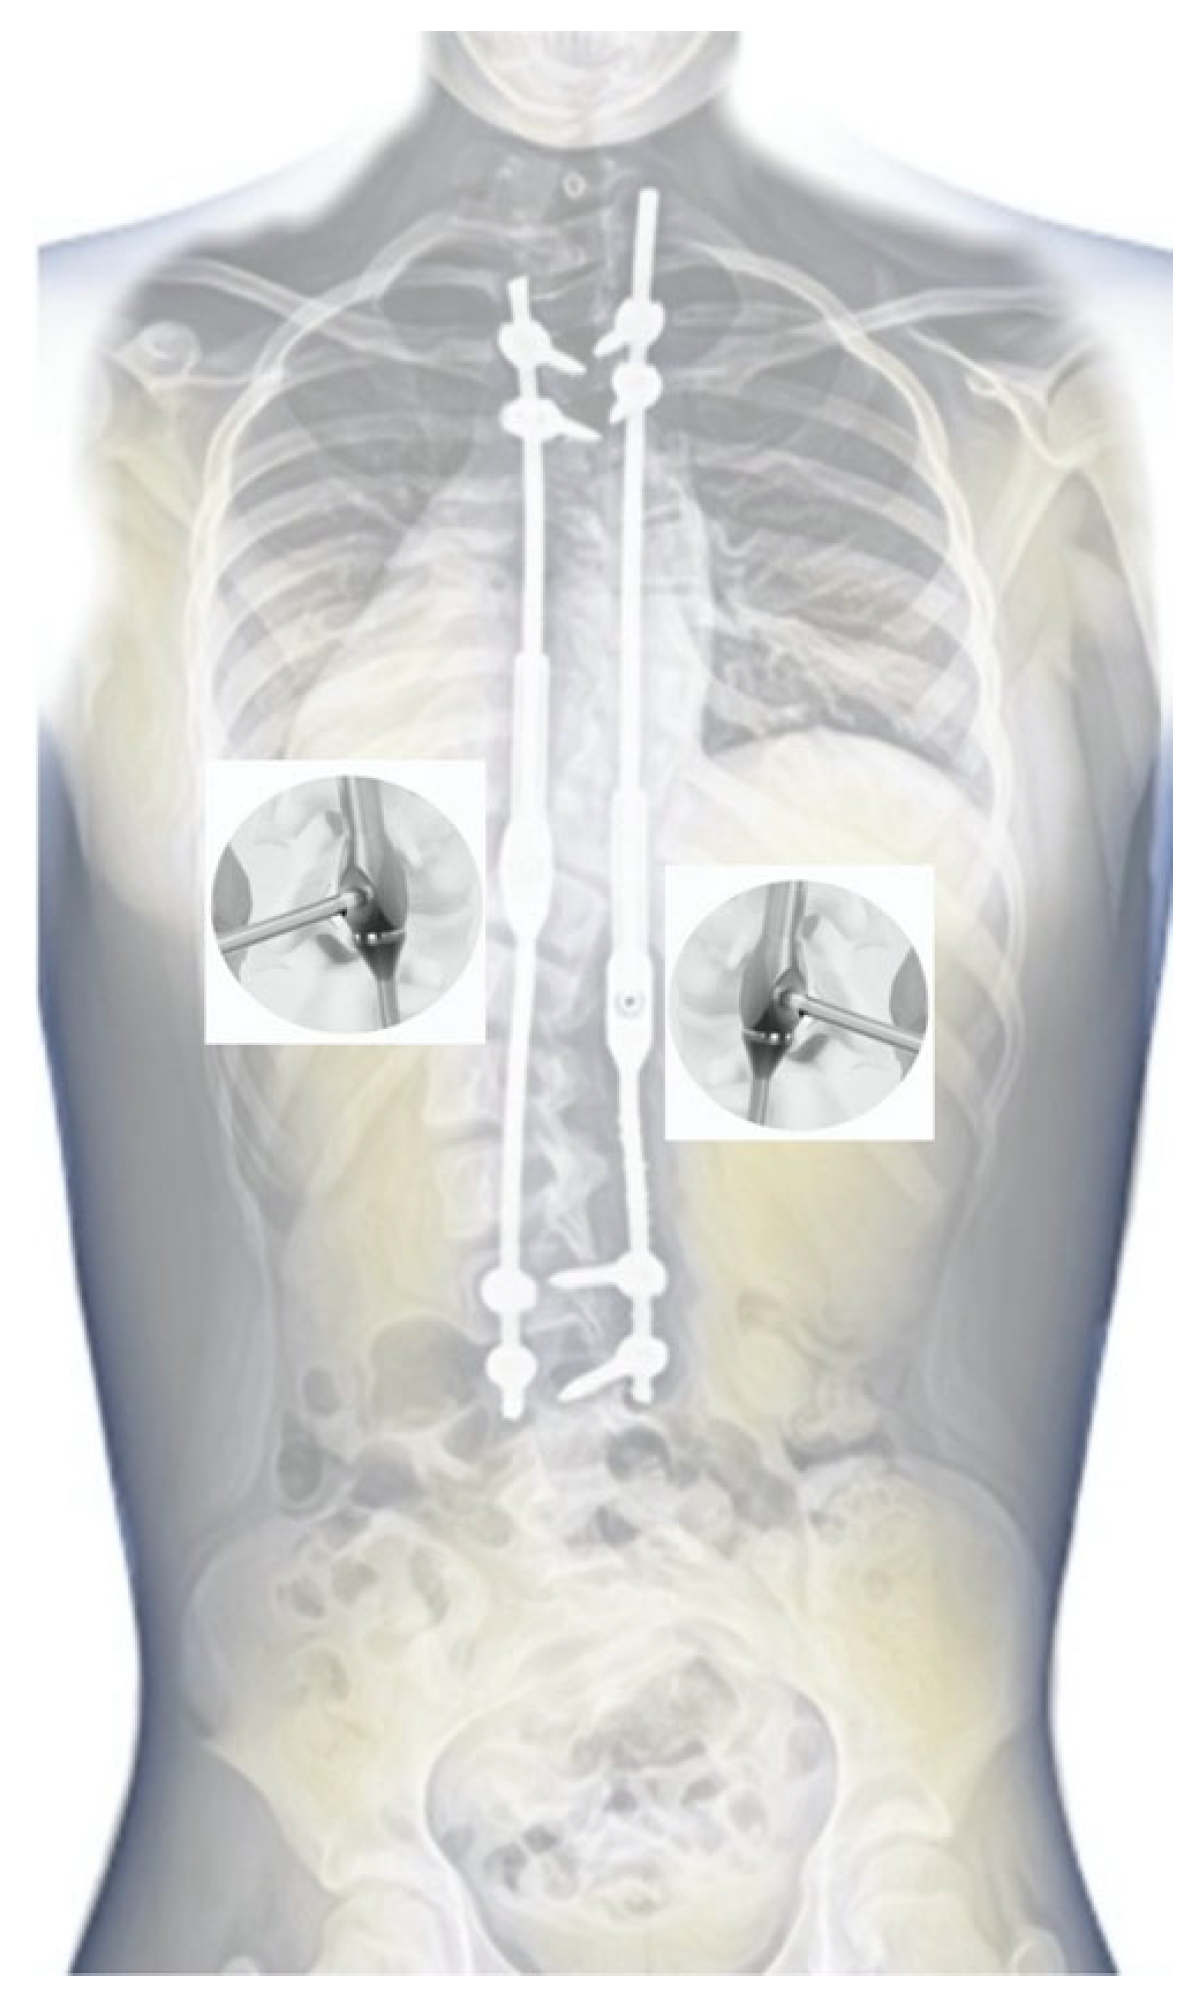

2.1. Surgical Technique

2.2. Example of Early-Onset Idiopathic Scoliosis